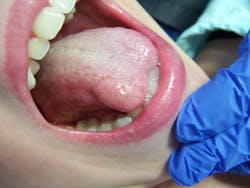

- Intraoral exam: A large, 1.5 cm raised lesion was noted on the right dorsal and lateral aspects of the tongue, extending to the underside. It was normal in color, slightly firmer than the surrounding area. It was not tender to palpation and inflammation was not present. Due to the size of the lesion, there was tenderness upon mastication and normal oral functions.

When asked about its presence, the parent stated that it had been there for eight years. Apparently, the patient had fallen when she was 5 years old and had bitten her tongue. Medical treatment or advice concerning the lesion was not pursued.

The clinical diagnosis is traumatic neuroma, also known as amputation neuroma or pseudoneuroma. This lesion results from a traumatic event to a nerve, such as severage. There is most often a history of laceration, surgery, or trauma. Most common locations are on the tongue, lip, or near the mental foramen.